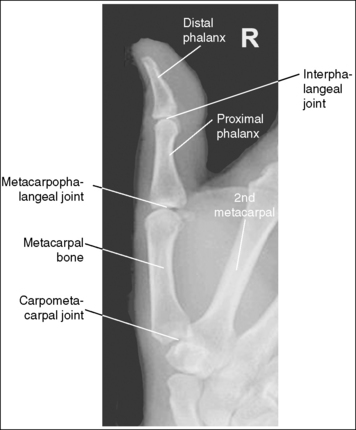

See Figure 4-1 and Box 4-2.

The finger demonstrates a PA projection. The soft tissue width and midpoint concavity are the same on both sides of the phalanges.

• Finger rotation is controlled by the amount of palm pronation. A PA projection is accomplished when the palm is positioned flat against the IR (Figure 4-2).

• Detecting finger rotation. Because the thumb prevents the hand from rotating laterally, medial rotation is the most common rotation error. Take a few minutes to study a finger skeleton, and note how the midpoints of the phalanges have equal side concavity when it is placed in a PA projection. Also, note that the anterior surface is concave, whereas the posterior surface is slightly convex. As the skeleton is rotated internally or externally, the amount of concavity increases on the side toward which the anterior surface is rotated, whereas the side toward which the posterior surface rotates demonstrates less concavity. The same observations can be made about the soft tissue that surrounds the phalanges. More soft tissue thickness is present on the anterior (palmar) hand surface than on the posterior surface, so the side demonstrating the greatest soft tissue width on an image is the side toward which the anterior surface was rotated. Look for this midpoint concavity and soft tissue width variation to indicate rotation on a PA finger projection (see Image 1). Note on a hand skeleton that the second metacarpal is the longest of the finger digits and that the length decreases with each adjacent metacarpal. This information can be used to determine whether the patient's finger was internally or externally rotated for a mispositioned PA finger image. If the finger was externally rotated, the aspect of the phalanges demonstrating the greater midpoint concavity faces the thumb or longer metacarpal (see Image 1). If the finger was internally rotated, the aspect of the phalanges demonstrating the greater midpoint concavity faces the shorter metacarpal.

The interphalangeal (IP) and metacarpophalangeal (MP) joints are demonstrated as open spaces, and the phalanges are not foreshortened.

• Open IP and MP joint spaces and unforeshortened phalanges are demonstrated when the finger is fully extended and the central ray is perpendicular and centered to the proximal IP (PIP) joint. This finger positioning and central ray placement align the joint spaces parallel with the central ray and perpendicular to the IR, as shown in Figure 4-3, resulting in open joint spaces. It also prevents foreshortening of the phalanges, because their long axes are aligned parallel with the IR and perpendicular to the central ray. The alignment of the central ray and IR with the joint spaces and phalanges changes when the finger is flexed. In Figure 4-4, note how finger flexion causes the phalanges to foreshorten and be superimposed on the joint spaces (see Image 2).

The PIP joint is at the center of the exposure field. The distal, middle, and proximal phalanges and half of the metacarpal are included within the collimated field.

• Direct a perpendicular central ray to the PIP joint to place the joint in the center of the image. Open the longitudinal collimation to include the distal phalanx and the distal half of the metacarpal. Transverse collimation should be within 0.5 inch (1.25 cm) of the finger skin line.